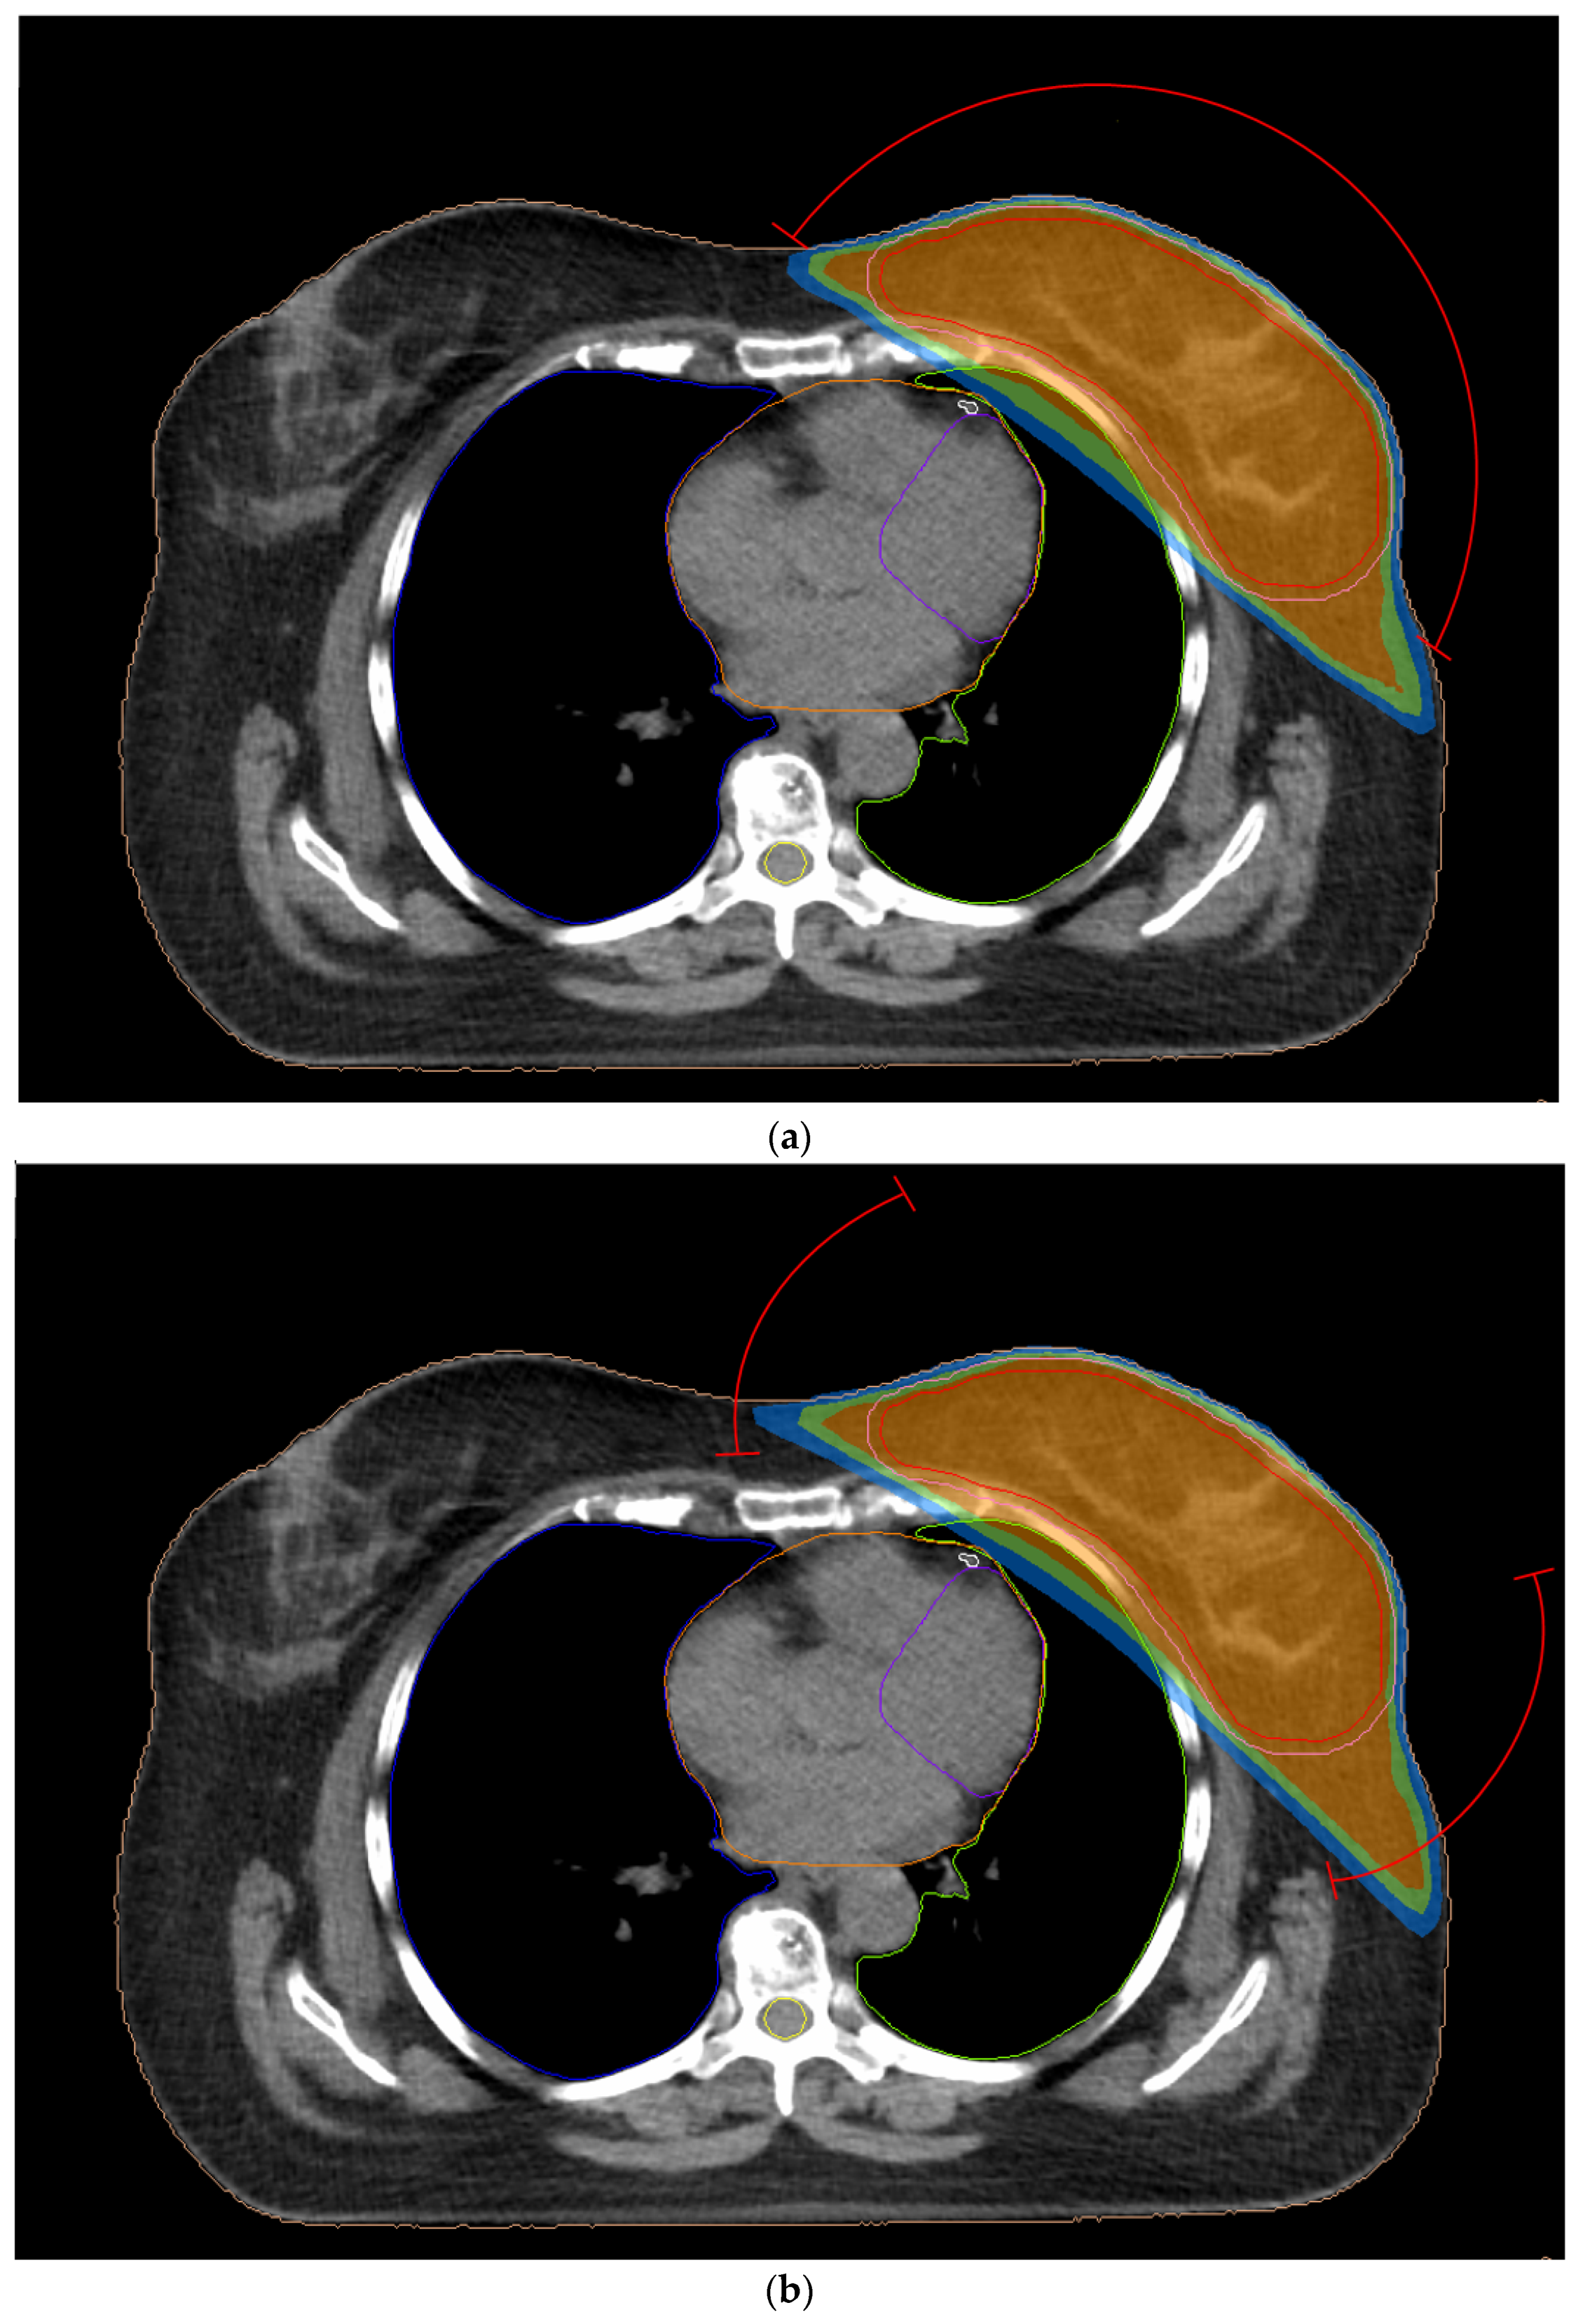

2.3.1. 3D-CRT Technique

2.3.2. Two-Field IMRT Technique (2F-IMRT)

2.3.3. Seven-Field IMRT Technique (7F-IMRT)

2.3.4. Two Partial-Arc VMAT Technique (VMAT1)

2.3.5. Four Partial-Arc VMAT Technique (VMAT2)